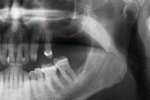

Panoramic radiograph of historic dental implants, taken 1978